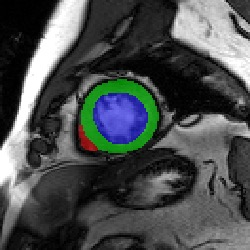

Transformers, the default model of choices in natural language processing, have drawn scant attention from the medical imaging community. Given the ability to exploit long-term dependencies, transformers are promising to help atypical convolutional neural networks (convnets) to overcome its inherent shortcomings of spatial inductive bias. However, most of recently proposed transformer-based segmentation approaches simply treated transformers as assisted modules to help encode global context into convolutional representations without investigating how to optimally combine self-attention (i.e., the core of transformers) with convolution. To address this issue, in this paper, we introduce nnFormer (i.e., Not-aNother transFormer), a powerful segmentation model with an interleaved architecture based on empirical combination of self-attention and convolution. In practice, nnFormer learns volumetric representations from 3D local volumes. Compared to the naive voxel-level self-attention implementation, such volume-based operations help to reduce the computational complexity by approximate 98% and 99.5% on Synapse and ACDC datasets, respectively. In comparison to prior-art network configurations, nnFormer achieves tremendous improvements over previous transformer-based methods on two commonly used datasets Synapse and ACDC. For instance, nnFormer outperforms Swin-UNet by over 7 percents on Synapse. Even when compared to nnUNet, currently the best performing fully-convolutional medical segmentation network, nnFormer still provides slightly better performance on Synapse and ACDC.